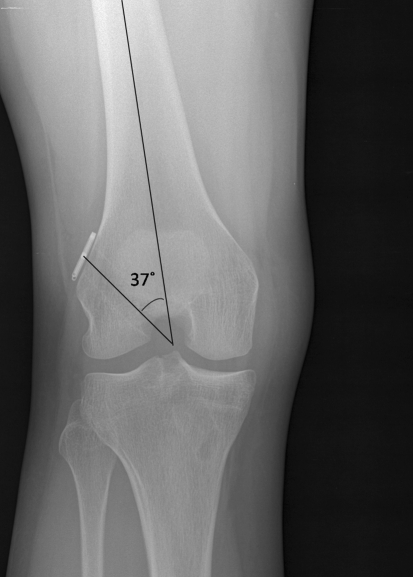

Radiographs were reviewed for all patients using the hospital system’s commercially available radiographic imaging system (Stentor, Philips Medical Imaging, Brisbane, CA, USA). The ACL tunnel angle was defined as the angle between the tunnel and the long axis of the femur (Fig. 1).

Fig. 1.

Anterior–posterior flexion weight-baring radiograph of the right knee after single-bundle ACL reconstruction. The tunnel angle is measured as the angle between the long axis of the femur and the outline of the tunnel